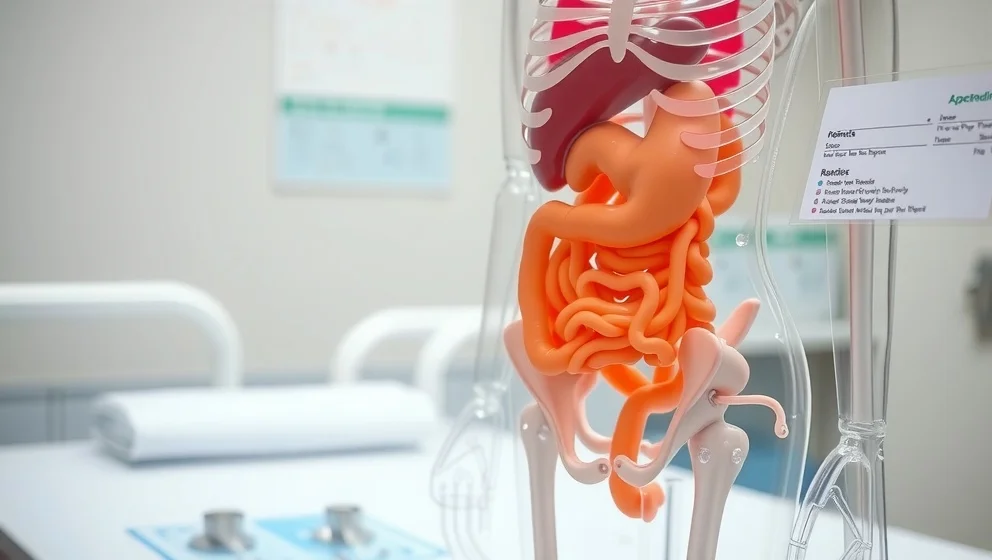

Buken ligger mellan revbenen och bäckenet. Du lär dig var de viktiga organen sitter och hur magen, levern och tarmen fungerar tillsammans.

Gallblåsan sitter gömt under levern på höger sida av magen. Du får veta vad gallblåsan gör och varför den är viktig för matsmältningen.

Levern sitter under höger revben och väger ungefär 1,5 kilo. Den är kroppens största inre organ och gör många viktiga jobb för att hålla dig frisk.

Njurarna sitter djupt inne i magen, på varje sida av ryggraden. Du får veta exakt var de ligger och vad de gör.

Blindtarmen sitter i nedre höger delen av magen. Du får veta exakt var den ligger och varför den kan bli inflammerad.